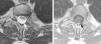

Tanto la tomografía computada (TC) como las radiografías convencionales de la columna cérvico-dorsal no mostraron hallazgos patológicos, pero la resonancia magnética (RM) de columna cérvico-dorsal evidenció un canal cervical estrecho debido a protrusiones discales múltiples y extrusión discal con compromiso neuroforaminal C6-C7 derecho. Incidentalmente se observó una imagen de bordes netos y aspecto quístico, con alta intensidad de señal en ponderación T2 y baja intensidad de señal en ponderación T1, sin realce tras la administración de gadolinio. Esta se localizaba a la altura del espacio intersomático D1-D2, en relación dorsal a la médula espinal (figs. 1–3).